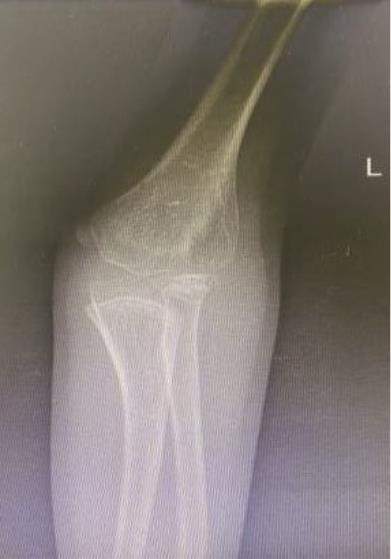

• 3D打印下精准截骨术治疗先天性尺桡关节脱位1例报道

2023, 48(5):618-620. DOI: 10.13406/j.cnki.cyxb.003218

摘要 (98) HTML (49) PDF 4.15 M (219) 评论 (0) 收藏

摘要: